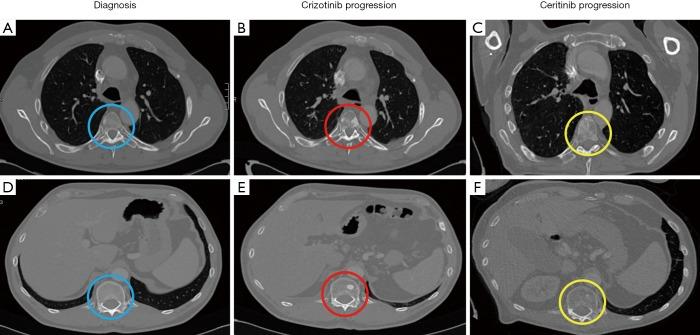

Tyrosine kinase inhibitors (TKIs) of the anaplastic lymphoma kinase gene () have significantly improved the quality of life and survival of non-small cell lung cancer (NSCLC) patients whose tumors harbor an translocation. However, most of these patients relapse within 2 to 3 years as the tumor acquires resistance mutations. Unlike beaming and digital PCR (dPCR), which only allow a few mutations to be analyzed, next-generation sequencing (NGS) approaches enable the simultaneous screening of multiple genetic alterations even when the frequencies of the variants are very low. We present the case of a 52-year-old man who was diagnosed with an -positive NSCLC and was treated with crizotinib and, subsequently, ceritinib. The analysis of serial liquid biopsies by NGS detected two asynchronous mutations arising in the locus during disease progression, namely p.Gly1269Ala (c.3806G>C) and p.Gly1202Arg (c.3604G>A), that conferred resistance to crizotinib and ceritinib, respectively. The resistance mutations were detected independently at different times, and could be imputed to different metastatic lesions, thereby highlighting the importance of heterogeneity in advance disease. Plasma levels of resistance mutations correlated well with tumor responses assessed by CT scans and bone scintigraphy, demonstrating that non-invasive tumor molecular profiling by NGS allows the efficient dynamic monitoring of -positive NSCLC patients, and outperforms dPCR and beaming because more somatic mutations can be tracked over the course of the treatment. In conclusion, this case report illustrates the usefulness NGS to guide therapeutic decisions in -positive NSCLC patients based tumor molecular profile upon disease progression.

间变性淋巴瘤激酶基因()的酪氨酸激酶抑制剂(TKIs)显著改善了肿瘤携带 易位的非小细胞肺癌(NSCLC)患者的生活质量和生存率。然而,这些患者中的大多数在2至3年内复发,因为肿瘤获得了耐药性突变。与仅允许分析少数突变的荧光定量PCR和数字PCR(dPCR)不同,新一代测序(NGS)方法能够同时筛查多个基因改变,即使变异频率非常低。我们报告了一例52岁男性患者,他被诊断为 阳性NSCLC,接受了克唑替尼治疗,随后接受了色瑞替尼治疗。通过NGS对系列液体活检进行分析,在疾病进展过程中检测到 基因座出现了两个不同时发生的突变,即p.Gly1269Ala(c.3806G>C)和p.Gly1202Arg(c.3604G>A),分别赋予了对克唑替尼和色瑞替尼的耐药性。耐药性突变在不同时间独立检测到,可能归因于不同的转移病灶,从而突出了晚期疾病异质性的重要性。 耐药性突变的血浆水平与CT扫描和骨闪烁显像评估的肿瘤反应密切相关,表明通过NGS进行的非侵入性肿瘤分子谱分析能够有效动态监测 阳性NSCLC患者,并且优于dPCR和荧光定量PCR,因为在治疗过程中可以追踪更多的体细胞突变。总之,本病例报告说明了NGS在根据疾病进展时的肿瘤分子谱指导 阳性NSCLC患者治疗决策方面的有用性。